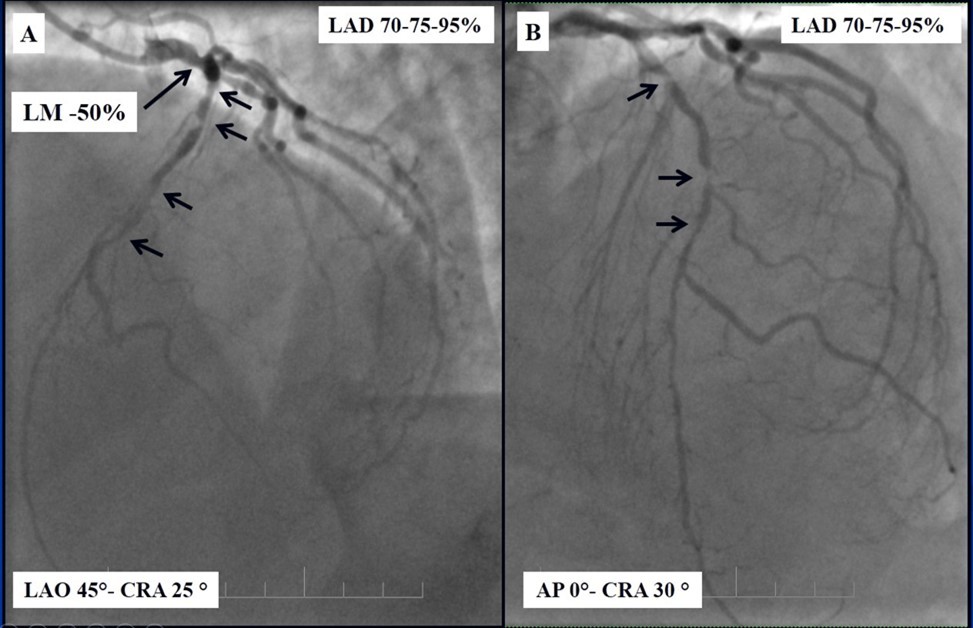

Angiography revealed rare anatomical variation LMCA quadrifurcation (Figure 1, Figure 2), 50% stenosis of the distal part of the LMCA, 40% stenosis of the ostial segment of left anterior descending (LAD) artery and diffuse prolonged 70-75-95% stenosis in mid-segment (Figure 3), 75% stenosis of the ostial segment of the circumflex (CX) artery, 75% stenosis of the ostial segment of the first marginal branch (OM1), 75-90% stenosis of the proximal segment of the intermediate artery (IMA), prolonged diffuse severe 90-95% stenosis of mid-segment of the right coronary artery (RCA) (Figure 4).

Figure 4.A - 50% stenosis of the distal segment of the LMCA; B - 70-75-95% stenosis in mid-segment of the LAD.